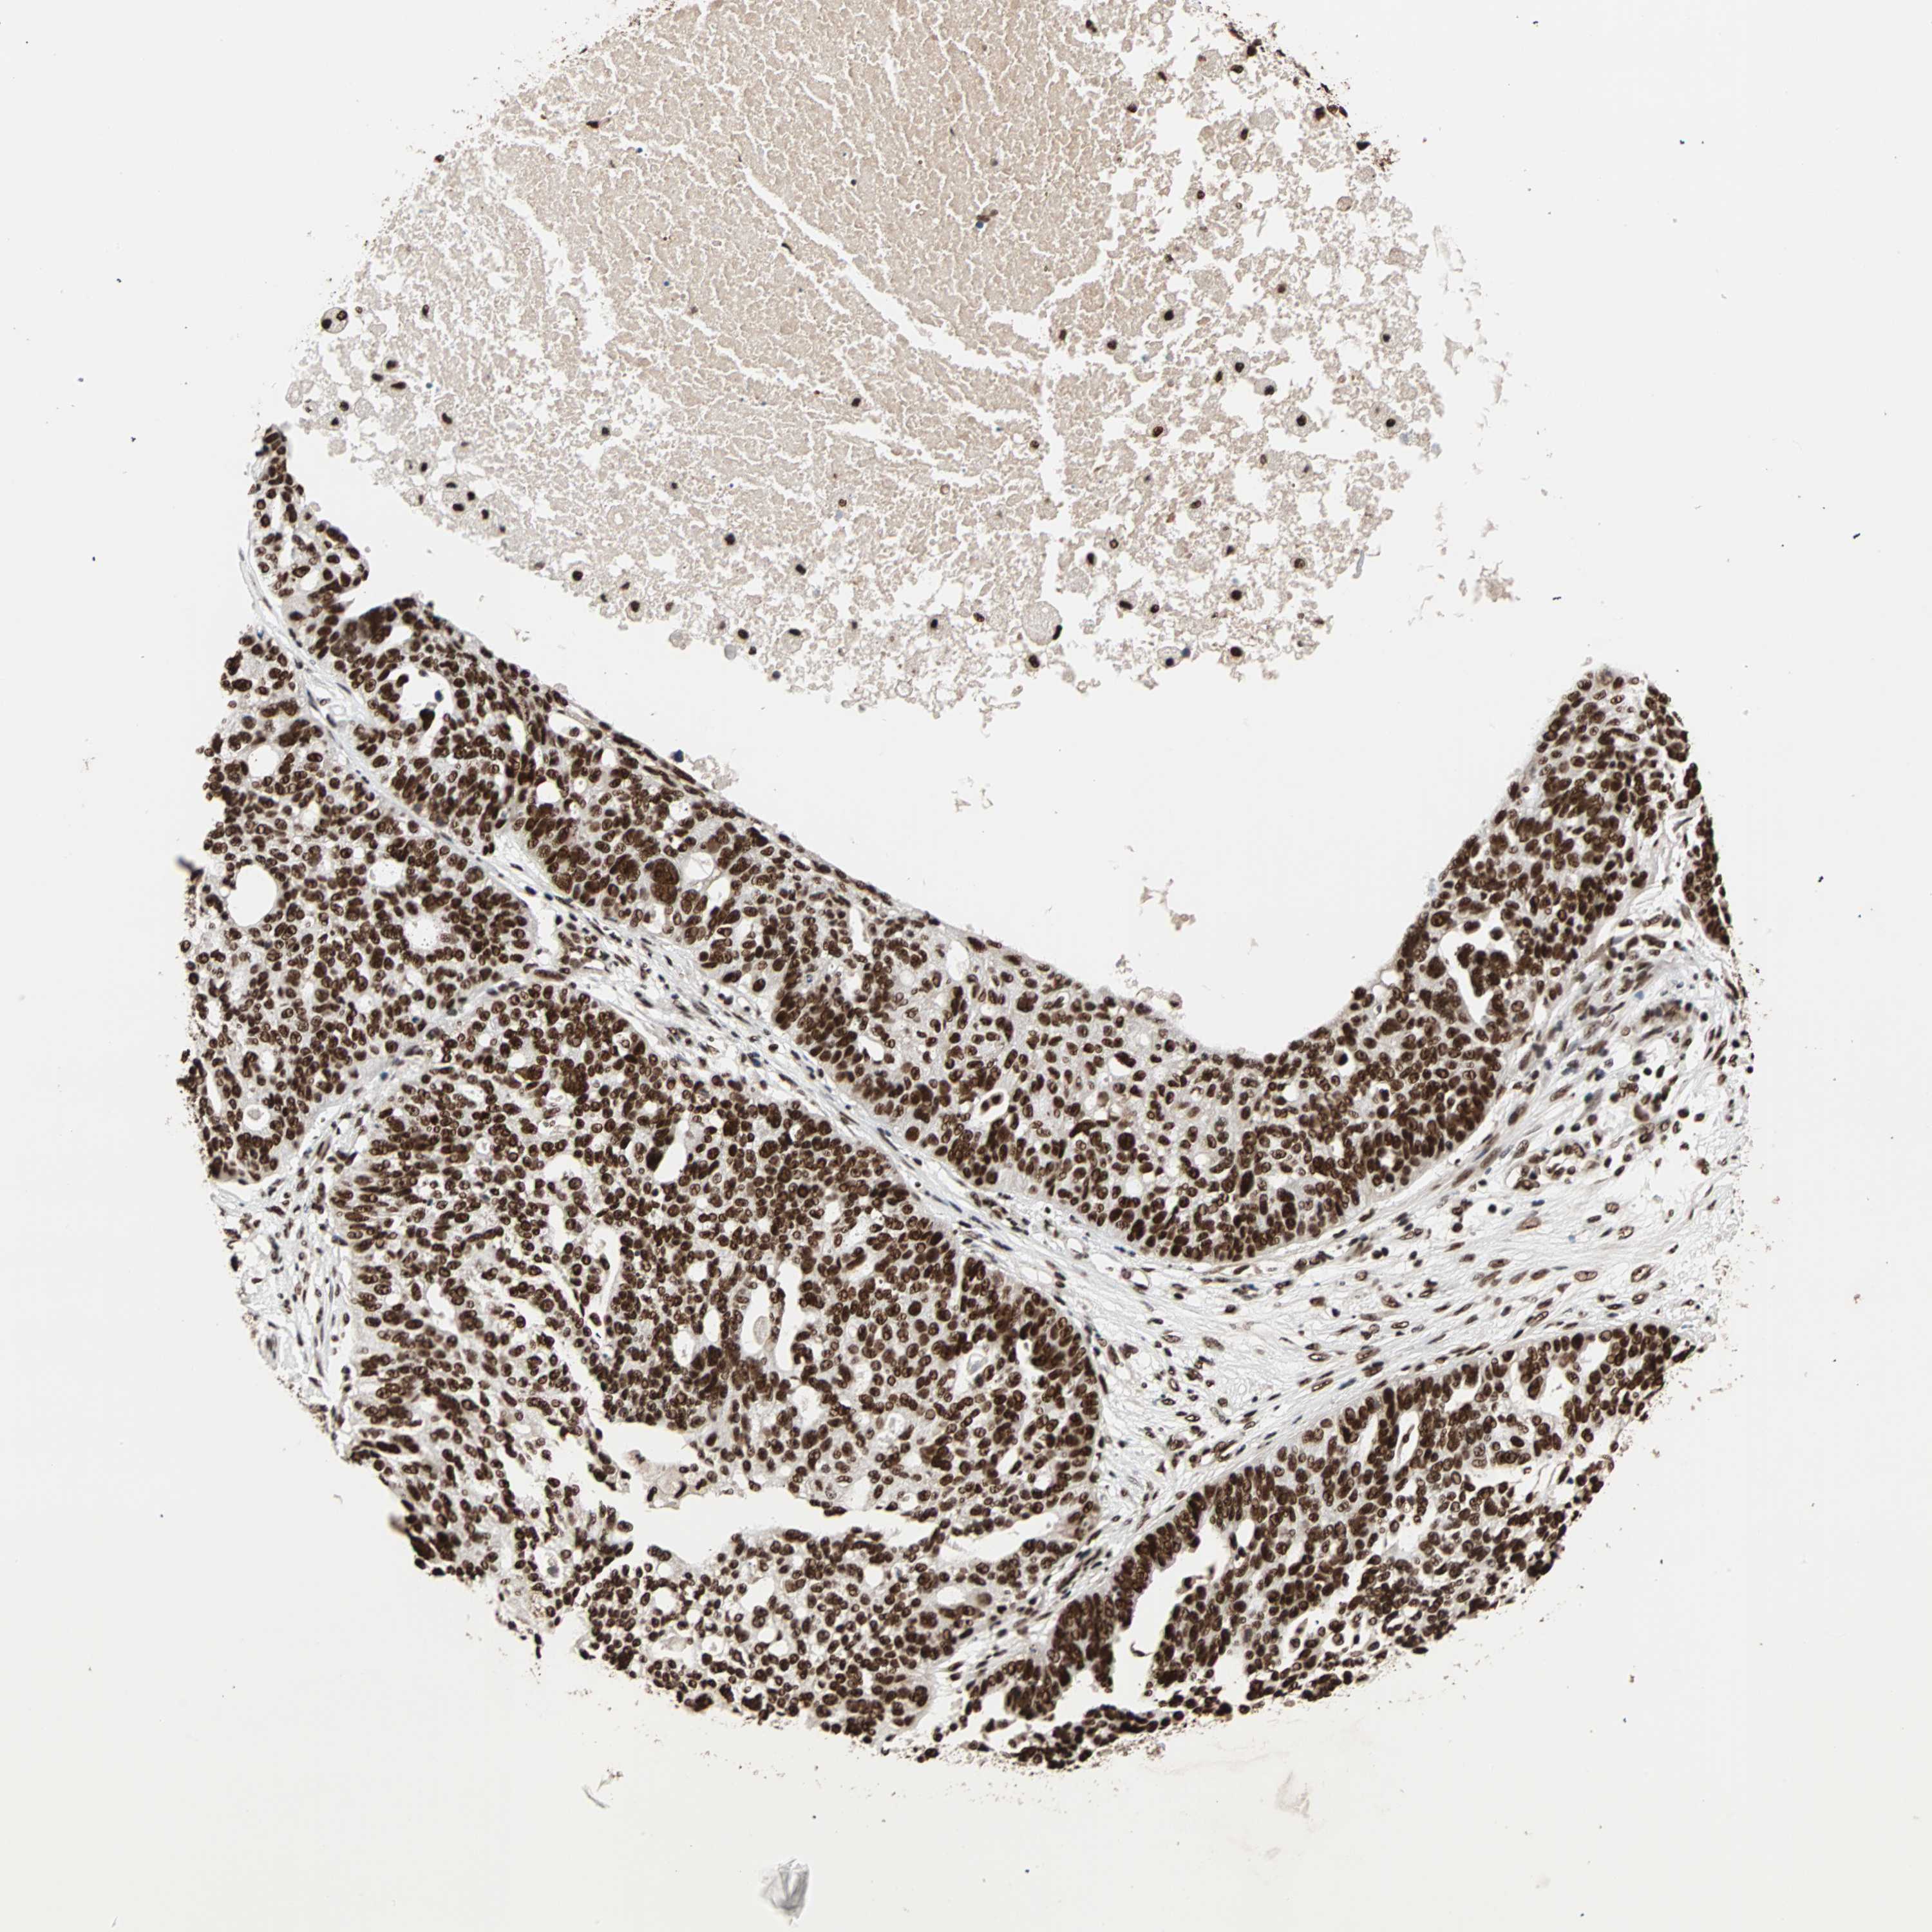

OVARIAN CANCER - Protein expressioni

A mouse-over function shows sample information and annotation data. Click on an image to view it in a full screen mode. Samples can be filtered based on level of antibody staining by selecting one or several of the following categories: high, medium, low and not detected. The assay and annotation is described here.

Note that samples used for immunohistochemistry by the Human Protein Atlas do not correspond to samples in the TCGA dataset.

Antibody stainingi

Antibody staining in the annotated cell types in the current human tissue is reported as not detected, low, medium, or high, based on conventional immunohistochemistry profiling in selected tissues. This score is based on the combination of the staining intensity and fraction of stained cells.

Each image is clickable and will lead to virtual microscopy that enables deeper exploration of all samples and also displays staining intensity scores, fraction scores and subcellular localization as well as patient and tissue information for each sample.

Antibody HPA007484

Staining

High

Medium

Low

Not detected

Intensity

Strong

Moderate

Weak

Negative

Quantity

>75%

75%-25%

<25%

None

Location

Nuclear

Cytoplasmic/membranous

Cytoplasmic/membranous,nuclear

Cystadenocarcinoma, serous, NOS

Carcinoma, endometroid

Cystadenocarcinoma, mucinous, NOS

Carcinoma, NOS